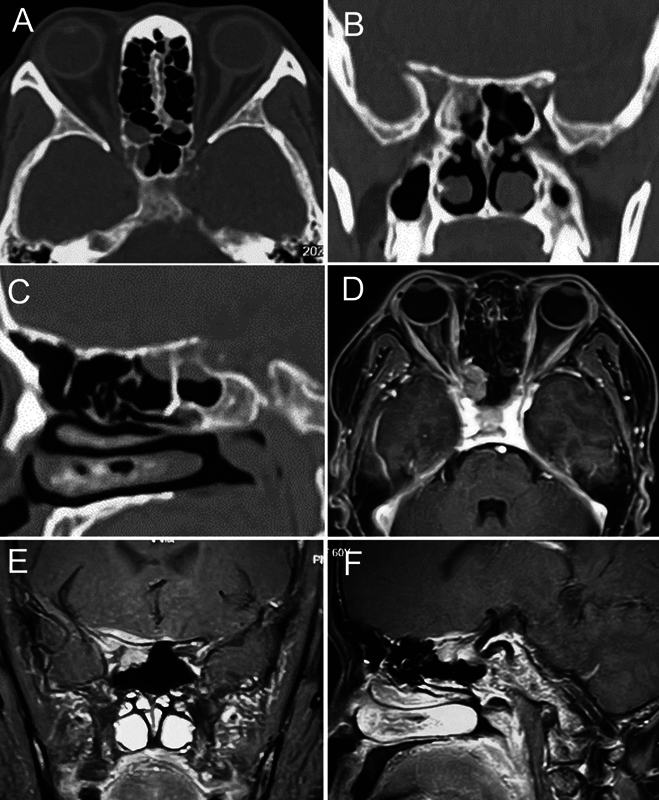

目标 最初表现在蝶窦、眶顶和颅底的多发性骨髓瘤(MM)极为罕见。本研究对其流行病学和研究进展进行了系统回顾。方法 通过检索 CNKI、万方数据、CQVIP 数据库、PubMed、Embase 和 Web of Science 来确定相关病例。此外,我们还发现了一例 IgD-λ(免疫球蛋白 D-lambda)MM,其最初症状为头晕、单侧疼痛、失明和眼球震颤,最终获得了 4 个月的总生存期。我们严格按照 PRISMA 标准纳入并总结了现有病例,并反映了我们的病例。结果 我们的系统综述包括 34 篇病例报告,发现 67.6% 的患者最初表现为复视,44.1% 的患者接受了内窥镜手术,其中只有两例为 IgD-λ 亚型。在我们的病例中,我们在内镜下进行了宽大的经蝶窦蝶窦切除术,并对颅底和眶顶病灶进行了活检。术后病理证实为高活性浆细胞瘤,临床诊断为IgD-λ MM,伴有TP53缺失突变和多发性髓外转移。采用了一系列诊断工具,包括血红蛋白、免疫球蛋白、尿蛋白分析、正电子发射断层扫描-计算机断层扫描(CT)、骨髓细胞学和基因检测。结论 鼻旁窦和颅底 IgD-λ MM 的临床表现不明显,妨碍了早期诊断。描述最初出现在这些部位的 MM 的文献很少。CT/磁共振扫描是确定特征性骨质破坏的必要手段。组织活检常用内窥镜方法。骨髓活检涂片、血清或尿蛋白电泳以及免疫固定电泳在出现靶器官损害时至关重要。

Objectives  Multiple myeloma (MM) with initial manifestations in the sphenoid sinus, orbital apex, and skull base is exceedingly rare. A systematic review was conducted to investigate the epidemiology and advancements . Methods  Relevant cases were identified by searching CNKI, WanFang Data, CQVIP databases, PubMed, Embase, and Web of Science. Additionally, we present a case of IgD-λ (immunoglobulin D-lambda) MM with initial symptoms of dizziness, unilateral pain, blindness, and ophthalmoplegia, leading to a 4-month overall survival. Strictly based on PRISMA standards, we included and summarized existing cases and reflected our case. Results  Our systematic review includes 34 case reports, revealing 67.6% of patients initially presented with diplopia and 44.1% underwent endoscopic procedures, notably with only two cases of IgD-λ subtype. In our case, we performed an endoscopic wide trans-ethmoidal sphenoidotomy and biopsy of the skull base and orbital apex lesion. Postoperative pathology confirmed a highly active plasmacytoma, clinically diagnosed as IgD-λ MM with a TP53 deletion mutation and multiple extramedullary metastases. A range of diagnostic tools was employed, including hemoglobin, immunoglobulin, urinary protein analysis, positron emission tomography-computed tomography (CT), bone marrow cytology, and gene detection. Conclusion  The subtle clinical manifestations of IgD-λ MM in the paranasal sinuses and skull base hinder early diagnosis. There is a paucity of literature describing MM initially presenting in these locations. CT/magnetic resonance scans are necessary to identify characteristic bone destruction. An endoscopic approach is popular for tissue biopsy. Bone marrow biopsy with a smear, serum or urine protein electrophoresis, and immunofixation electrophoresis are crucial upon the appearance of target organ damage.